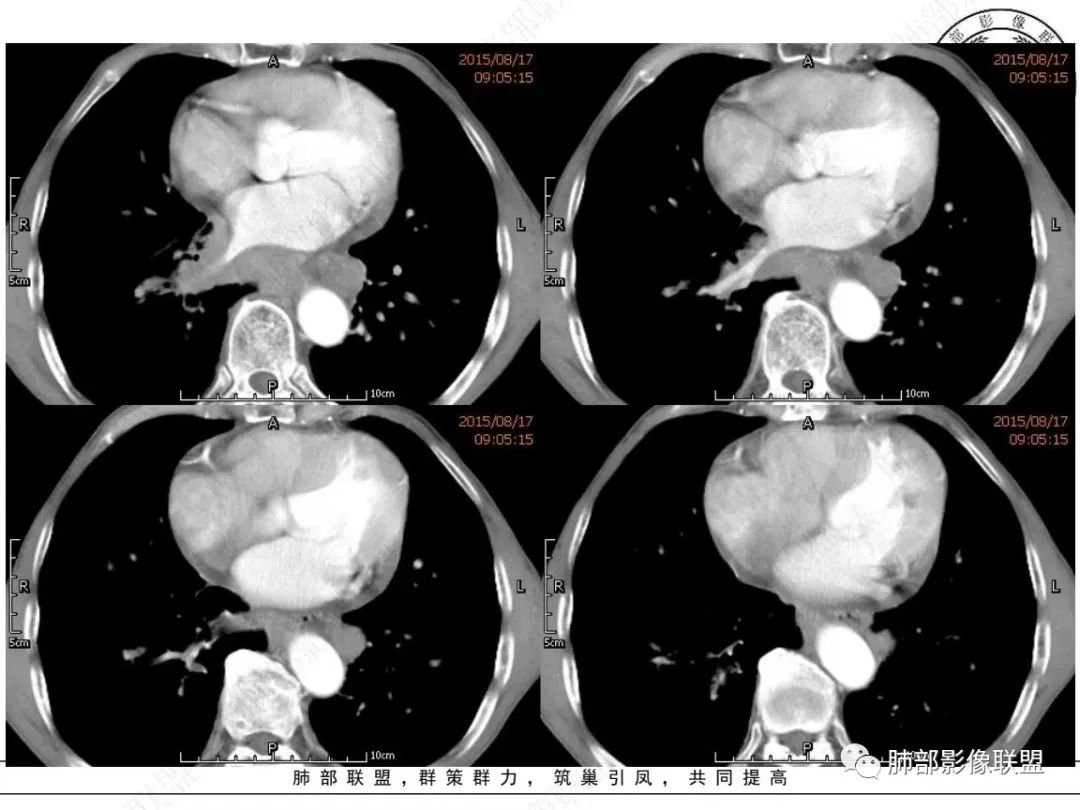

谢加平:纵隔内中后纵隔及右肺门淋巴结肿大,形成大肿块,整体密度均匀,并轻度强化,见“血管飘浮”征,包绕气管分叉及右主支气管及中间段支气管明显受压狭窄,并包埋右肺门血管束,无侵蚀破坏,右肺动脉后壁见压迹影,右肺下叶背段有阻塞性炎症,首选淋巴瘤,支气管超声内镜活检,明确诊断!

尘缘:淋巴瘤可能大于小细胞。

理由:四点,1、整个病灶位于纵隔中央后主,且以后纵隔为主,2、病灶内血管漂浮,3、肺内无原发灶,没找到“娘”。4、颌下淋巴结穿刺未找到小细胞癌。所以肯定先考虑淋巴瘤。

南边:

老年男性,颈部淋巴结而来,双侧对称,长期吸烟,双侧腋窝淋巴结肿大

,纵隔淋巴结肿大,特别是后纵隔,食道推移包绕,右肺门区支气管被包绕、受压狭窄。恶性应该没问题,问题是如何鉴别小细胞与淋巴瘤?

1、颈部、腋窝双侧淋巴结对称

2、右肺门区淋巴结肿大,但是没有沿支气管朝外延伸

3、食道没有梗阻

4、血管漂浮,走形自然

支持淋巴瘤